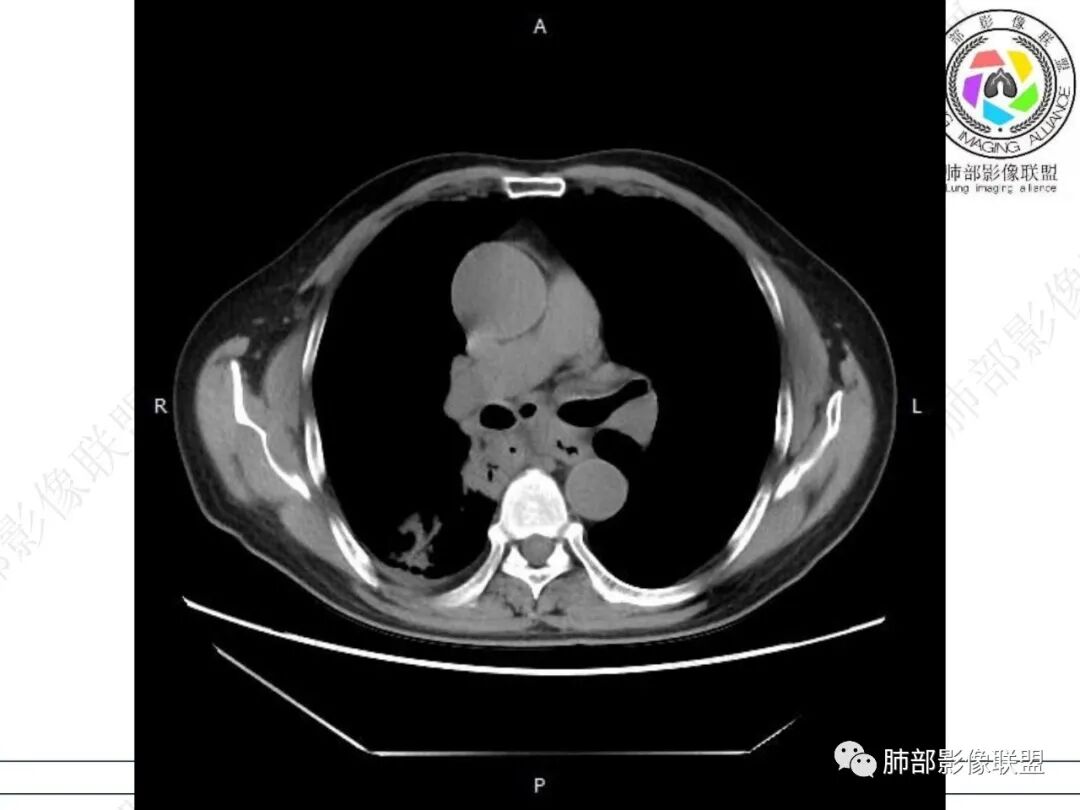

气管隆突下团片影,其内积气,与食道分界不清,食道壁增厚,管腔狭窄,右下肺实变影,支气管壁增厚,考虑食管支气管瘘并右下肺感染,食道肿瘤病变不除外

支持食管支气管瘘(考虑食管癌)伴后纵隔及右肺感染,食管管壁明显增厚,管腔狭窄,相邻右侧后纵隔内软组织内可见气体影,与食管分界不清,右肺有实变及不张。

右肺下叶背段条片状实变影,内可见支气管走行,支气管有狭窄有扩张,周围可见磨玻璃影,隆突下团片影,内密度不均可见气体影,与周围结构界限不清。食管下段壁增厚,管腔狭窄,右肺下叶慢性炎、肺不张,考虑食道肿瘤所致气管食管瘘。

右肺下叶沿肺叶肺段分布斑片、条片状影,以下叶背段为显,边缘模糊,内可见支气管走行,局部支气管管壁增厚,右侧胸腔少量积液。纵隔隆突下可见不均匀软组织密度影,与周围结构分界不清,内见气体密度影,与食管及相邻右肺支气管之间未显示通道。邻近食管下段壁明显不规则增厚,增强后食管管壁明显不均匀强化,可见线样强化的连续完整粘膜影。

3.综合分析:

右肺下叶片影,气道相关,符合感染性病变。纵隔隆突下软组织密度影,异常气体影,长病程,起病缓慢,提示存在气管或食管瘘。食管镜未见明显新生物形成,临床未提供进食或饮水呛咳临床表现,综合分析应该考虑支气管瘘的形成。

对比患者3月份的CT图,原隆突下存在增大钙化淋巴结,现在出现气体影,且钙化显示不清,应想到淋巴结结核破溃成瘘可能性。